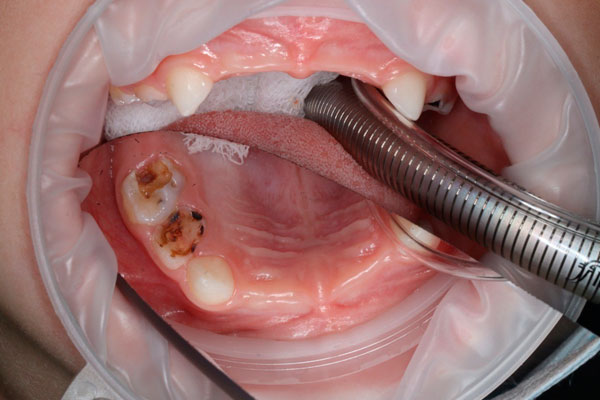

Лечение кариеса постоянного зуба

от 12619 ₽

Лечение постоянных зубов у детей: фото До и После